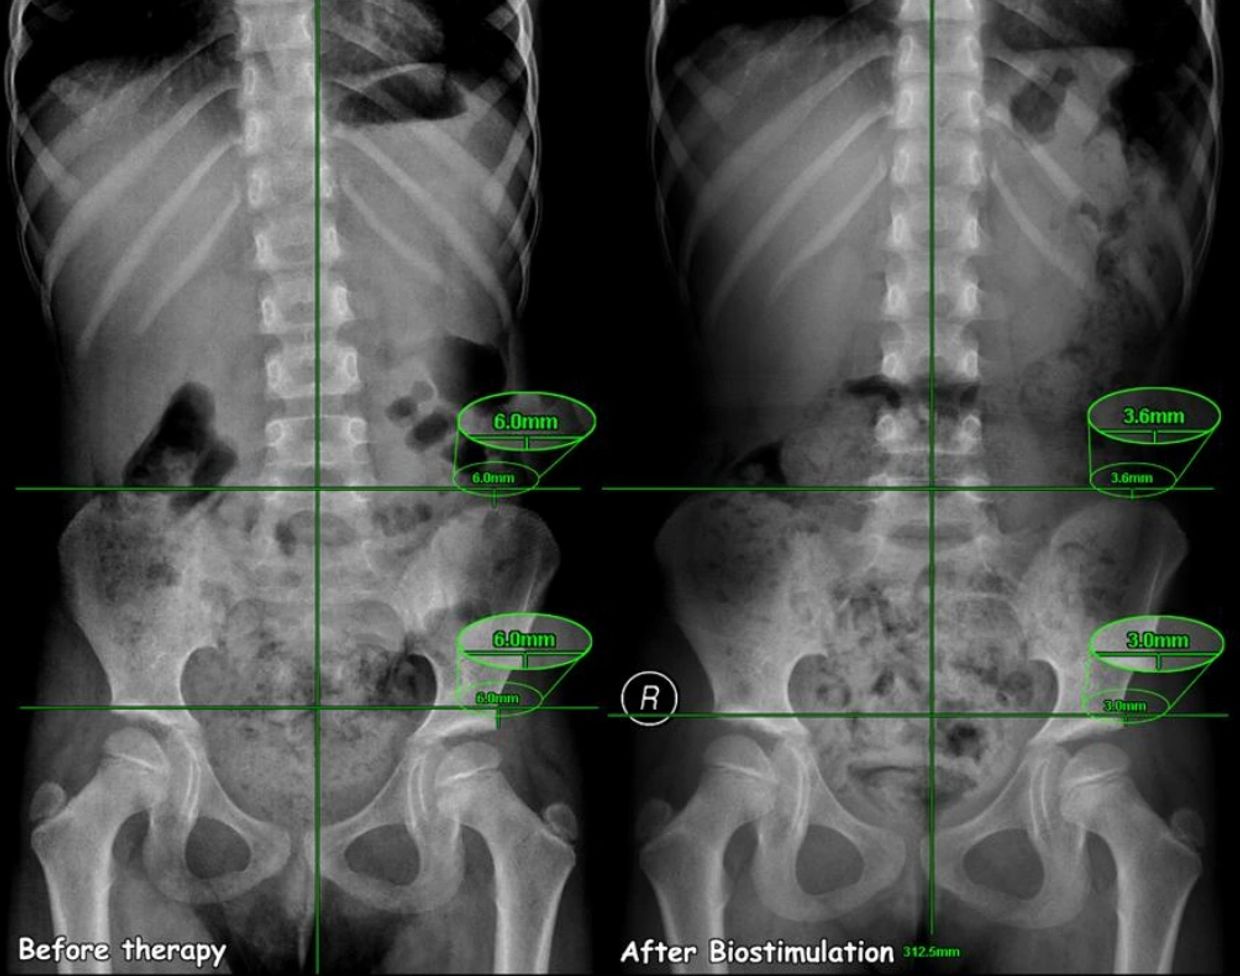

Paciente sofria com dores no pescoço e ombro esquerdo, o RX inicial mostrava ma posição da clavicula. foi aplicada 2 minutos de bioestimulação no modo Infinity em uma potencia agradável para paciente.

Podemos observar que apesar de uma aplicação simples houve 43% de melhora no posicionamento da clavicula.

Cedido para Dr. Jerry Tennant pelo Dr. Ali Al-Tubaikh, MD Sabah Hospital, Kuwait City, Kuwait